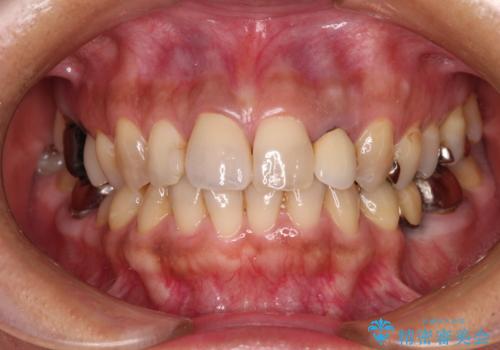

- 保険診療でのクラウンが変色してしまったとのことで来院された患者様です。

根管治療がされていなかったため、まずは根管治療を行い、その後オールセラミッククラウンにて補綴することとしました。

左上の歯も歯肉縁部分にメタルの色が見えており、合わせて治療することをお勧めしましたが、今回は1歯のみを治療することとしました。